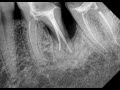

Периодонтит